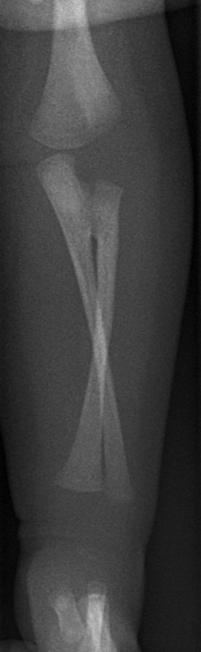

Een aterm meisje dat via een sectio caesarea geboren was, lag opgenomen in verband met een hyperbilirubinemie. Op grond van uiterlijke kenmerken was er een sterk vermoeden van het syndroom van Down, dat door chromosomenonderzoek werd bevestigd. Daarnaast viel op dat zij haar linker arm beduidend minder gebruikte en dat de stand van de linker onderarm afweek ten opzichte van rechts.

Wat is uw diagnose?